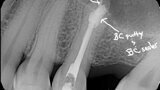

Fig. 16a: Case treated with a Bioceramic master cone, sealer and putty. Note the excellent apical control in this blunderbuss apex. (Courtesy of Dr. Rico Short)

Fig. 16b: Case treated with a Bioceramic master cone, sealer and putty. Note the excellent apical control in this blunderbuss apex. (Courtesy of Dr. Rico Short)